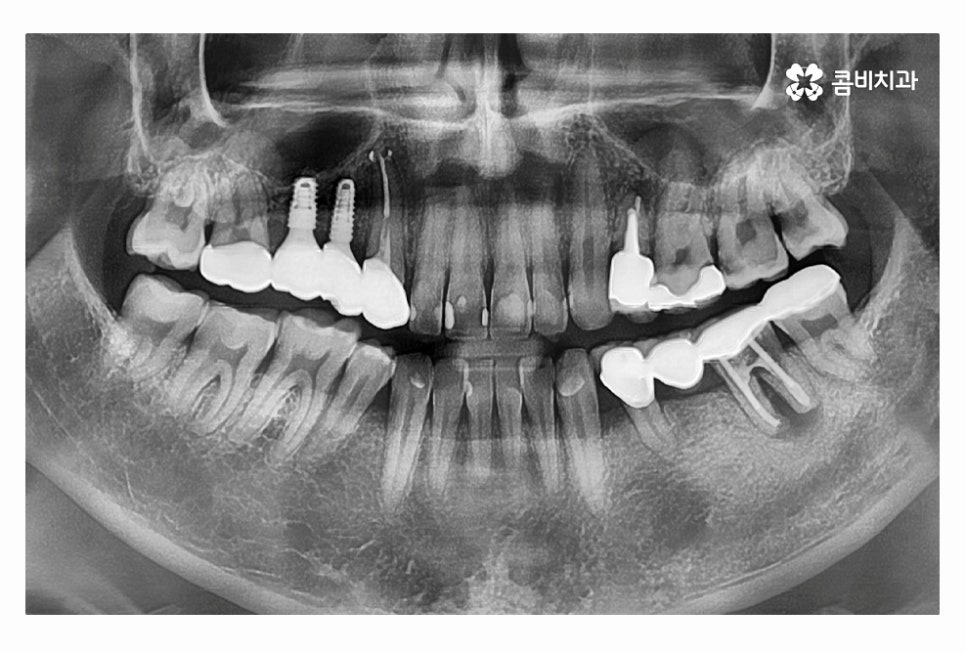

임플란트의 치료 계획은 치아를 잃게 된 원인부터 잇몸 상태,

전신질환 여부, 회복력 등을 고려하여 1:1로 맞춤 치료 계획을 세우며

자연치아를 대체하는 치료인 만큼 치료 결과도 중요하지만

수명을 오랫동안 건강하게 유지하는 것이 관건이라고 할 수 있는데요.

특히 20대임플란트 치료를 하시는 분들의 경우 앞으로 되도록

오랜 기간 건강하게 임플란트 수명을 유지해야 하며

부작용에 주의해야 하기 때문에 오랫동안 믿고 찾을 치과의 선택이 중요할 수 있어요.